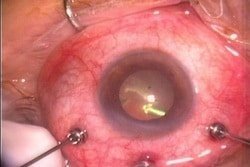

Figura 1 a y b. Antiguamente vitrectomía por 20G con suturas de la esclera y apertura conjuntival posteriormente cerrada con puntos.